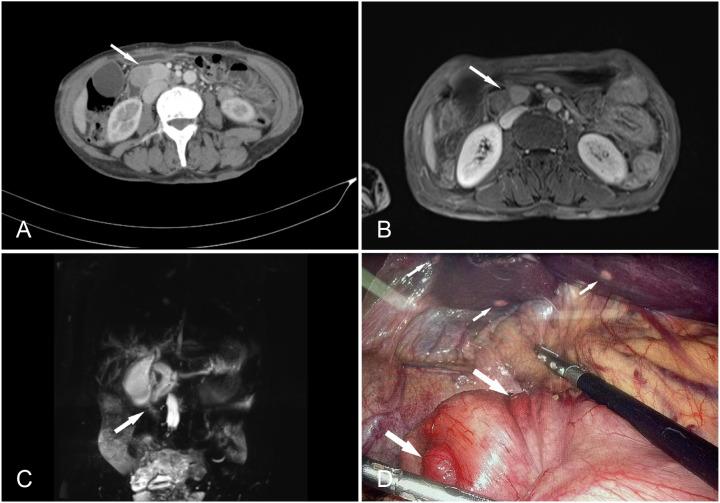

Neurofibromatosis type 1 (NF-1) is commonly associated with a variety of rare tumors. However, no case of multiple gastric gastrointestinal stromal tumors (GISTs) or duodenal ampulla neuroendocrine tumors (NETs) with multiple liver metastases in a patient with NF-1 has yet been reported. Here, we describe a case of a 55-year-old female patient with NF-1 whose serum Pro-Gastrin-Releasing Peptide (pro-GRP) levels were elevated. Gastrointestinal endoscopy and biopsy showed duodenal papilla space-occupying mass, and the pathological diagnosis turned out to be neuroendocrine tumors (NETs). During surgical exploration, multiple tumors were found on the serosal surface of the stomach and numerous miliary metastases in the liver. Following histopathological examination, it was determined that the liver metastases were NF-1 and the tumors in the gastric wall were GISTs. The patient benefited from targeted therapy and had an uneventful hospital stay. In this case, we emphasize treating patients with neurofibromatosis type 1 who exhibit abdominal symptoms with a high degree of clinical suspicion and performing thorough evaluations to rule out multiple tumors.

1型神经纤维瘤病(NF-1)通常与多种罕见肿瘤相关。然而,尚未有关于1型神经纤维瘤病患者出现多发胃胃肠道间质瘤(GISTs)或十二指肠壶腹神经内分泌肿瘤(NETs)并伴有多发肝转移的病例报道。在此,我们描述了一名55岁患有NF-1的女性患者,其血清胃泌素释放肽前体(pro-GRP)水平升高。胃肠内镜检查及活检显示十二指肠乳头占位性肿块,病理诊断为神经内分泌肿瘤(NETs)。手术探查时,在胃浆膜表面发现多个肿瘤,肝脏有大量粟粒样转移灶。经组织病理学检查,确定肝脏转移灶为NF-1,胃壁肿瘤为GISTs。该患者受益于靶向治疗,住院期间病情平稳。在此病例中,我们强调对于出现腹部症状的1型神经纤维瘤病患者要高度临床怀疑,并进行全面评估以排除多发肿瘤。